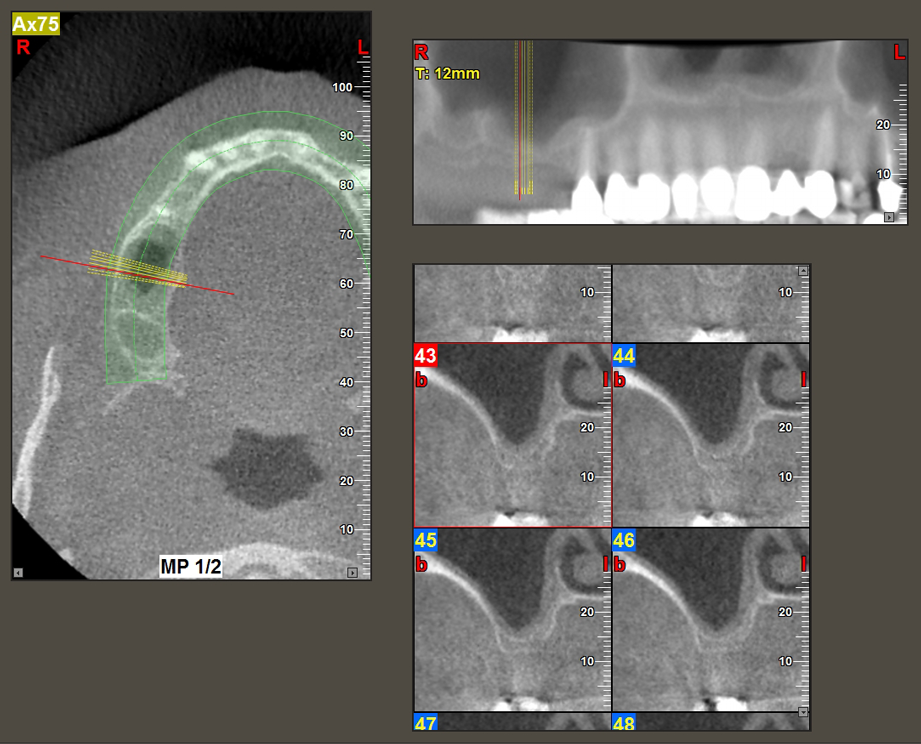

A 49-year-old female patient, a non-smoker and with nothing remarkable in her general medical history, was referred to our oral surgery practice for surgical extraction of tooth 16 and subsequent implantation. After the extraction, the patient experienced mild sinusitis trouble with the resultthat we initially waited six months before carrying out the measure. The residual bone height at the planned implant position measured 3-4 mm (Fig. 1 and 2).

To move the augmentation material in the direction of the maxillary sinus atraumatically, the implant was inserted very slowly by hand (Fig. 9). In the process, the membrane was pushed in the cranial direction once again. After two months, the surgical site healed without irritation. Six months later, the x-ray check showed a significant increase in opacity as an indication of ossification (Fig. 10). The prosthetic restoration was carried out with a metal-ceramic crown.